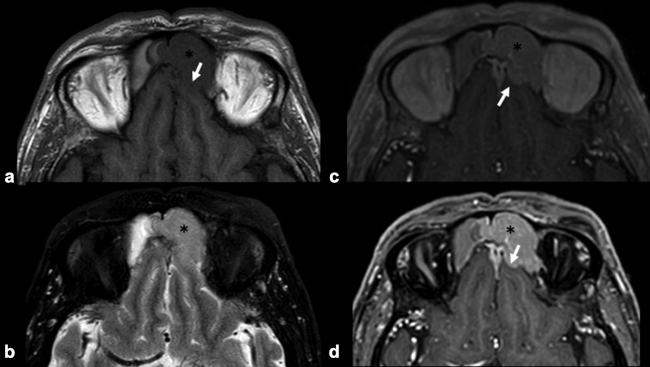

La TC de corte fino (espesor de corte de 1 mm) con reconstrucciones en plano coronal y sagital, es la mejor prueba de imagen inicial para el estudio del NBO. En la TC, aparece como una masa homogénea de tejido blando en la bóveda nasal con realce moderado y uniforme (►Figs.1y2). Se pueden encontrar calcificaciones punteadas dispersas (►Figs.2,3,4,5a,6).50 El valor principal de la TC es una mejor definición de la afectación ósea en comparación con la RM. La TC ayuda a evaluar la erosión ósea de la placa cribiforme, la fóvea etmoidal y la lámina papirácea (►Figs.1,2,3,4,5a,8). Sin embargo, la remodelación ósea sin erosión puede presentarse en algunos casos debido a su patrón de crecimiento indolente.3,35,49 Los estudios de TC generalmente revelan un patrón lítico y muy raramente hiperostosis dominante que simula displasia fibrosa.51 La TC también es útil para evaluar la presencia de metástasis regionales en cuello y a distancia.52,53

La RM es la prueba de imagen de elección para evaluar los detalles de la extensión y la estadificación locorregional del tumor. La RM es superior a la TC para determinar el grado de afectación del tejido blando (►Fig. 9) con una mejor evaluación de la afectación intracraneal (►Figs.10,11,12,13,14), orbital (►Figs.14y15), de la base del cráneo y la invasión perineural.53,54 La RM tiene un valor añadido para distinguir la afectación dural de la del parénquima cerebral (►Fig. 12).55 En la RM, el NBO aparece hipointenso respecto a la sustancia gris en imágenes ponderadas en T1 y de isointenso a hiperintenso en las imágenes ponderadas en T2 (►Figs.10,11,12,13,14,15).56 Muestra un realce homogéneo, excepto en áreas con hemorragia o necrosis. Además, permite diferenciar las secreciones retenidas del tumor, al ser estas hiperintensas ponderadas en T2.53,55 Los hallazgos de imágenes clásicos incluyen una masa “en forma de mancuerna” que se extiende a través de la placa cribiforme (►Fig. 12), con la parte estrecha a nivel de la placa. Los quistes tumorales periféricos (►Figs.5b,12,14,16) y las calcificaciones moteadas son bastante característicos de NBO.1

La evaluación del tumor recurrente debe incluir tanto TC como RM. Las características de imagen del tumor recurrente no difieren de su apariencia en la presentación inicial. Se ha sugerido el siguiente protocolo de seguimiento para detectar precozmente las recurrencias: RM con contraste 2-4 meses después de completar todo el tratamiento. Posteriormente, se repite cada 4-6 meses durante 5 años, y pasado ese tiempo, se realiza anualmente durante la vida del paciente.59 El protocolo de RM utilizado en nuestro servicio consiste en la realización de secuencias ponderadas en T1, T2 y T1 con supresión grasa sin y con contraste para el estudio a nivel nasosinusal y secuencias ponderadas en T1, T2, FLAIR, DW-EPI y T1 con contraste para el estudio encefálico. Además, se debe hacer una radiografía de tórax anual para excluir la presencia de metástasis.59